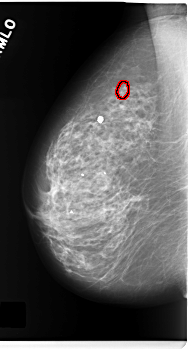

C_0171_1.RIGHT_MLO

FILE: C_0171_1.RIGHT_MLO.OVERLAY

TOTAL_ABNORMALITIES 1

ABNORMALITY 1

LESION_TYPE CALCIFICATION TYPE PLEOMORPHIC DISTRIBUTION CLUSTERED

ASSESSMENT 4

SUBTLETY 4

PATHOLOGY MALIGNANT

TOTAL_OUTLINES 1

BOUNDARY